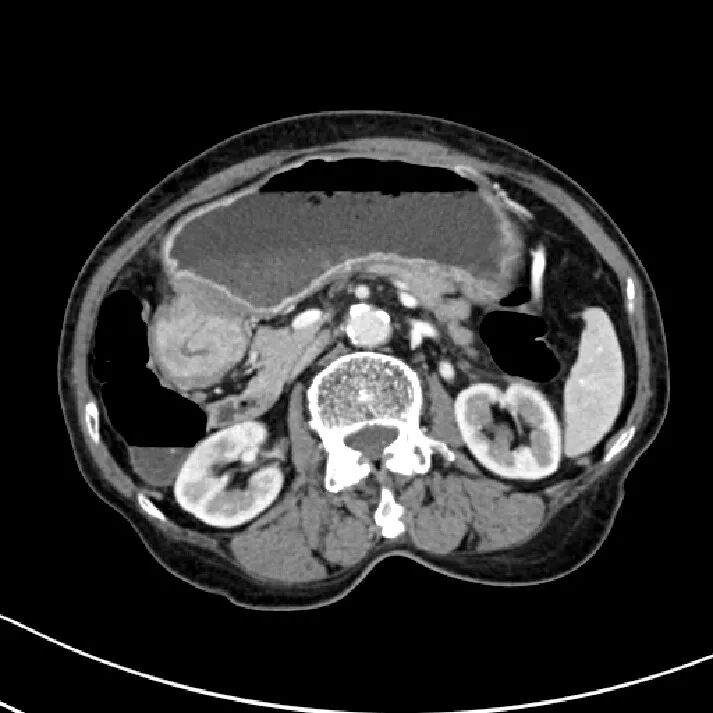

胃癌

进展期胃癌CT检查有利于观察病变的侵犯范围和淋巴结转移情况

升结肠癌并广泛转移

升结肠癌并肝转移